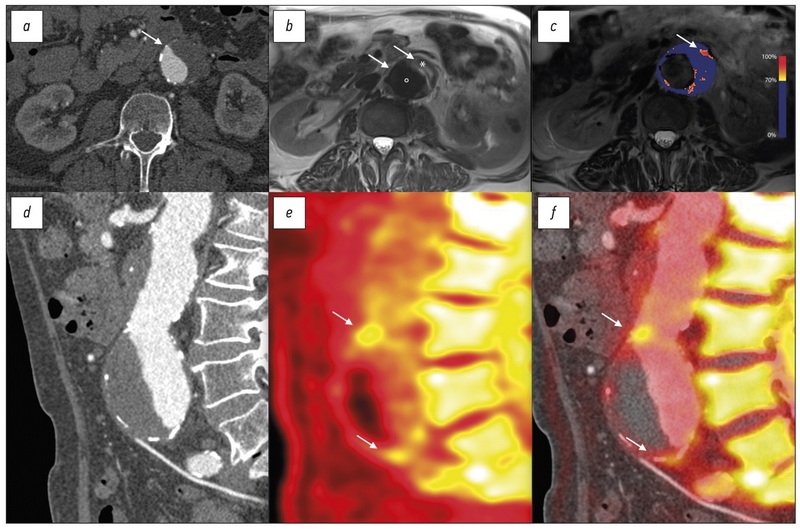

- Forsythe R.O., Dweck M.R., McBride O.M., et al. 18F-Sodium fluoride uptake in abdominal aortic aneurysms: the SoFIA3 study//J Am Coll Cardiol. 2018. Vol. 71, N 5. Р. 513–523. doi: 10.1016/j.jacc.2017.11.053